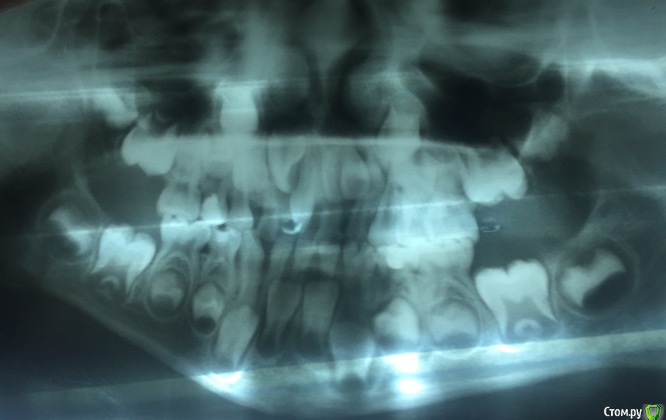

Vitalina_angel Опубликовано 20 апреля, 2016 Автор Поделиться Опубликовано 20 апреля, 2016 Вот вроде получилось, надеюсь посмотрите и мне расскажите что и как. Ссылка на комментарий

___49___ Опубликовано 20 апреля, 2016 Поделиться Опубликовано 20 апреля, 2016 (изменено) По снимку определяется сдвиг зачатка 22 зуба в сторону клыка за счет контакта с вестибулярной поверхностью зачатка 21 зуба повернутого по оси на 90 градусов из-за сверхкомплектного зуба. Путь удаления S вижу с вектором направленным к центральной линии под острым углом, захват с предварительным рассечением по гребню от 51 до 62 с последующей отслойкой ,и малыми ротационными движениями должен прекрасно извлечься без всякого "ковыряния". .. и с более благоприятным отдаленным результатом. ИМХО. Расписал удаление подробно для коллег - если ошибаюсь - поправьте . Изменено 20 апреля, 2016 пользователем ___49___ Ссылка на комментарий